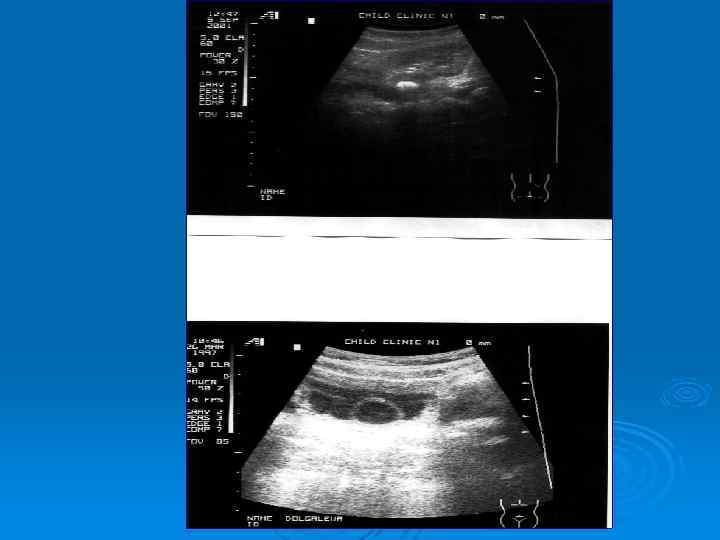

Утолщение стенки лоханки при остром пиелонефрите

Абсцесс верхнего полюса почки у ребенка, 11 лет

Рентгенконтрастное исследование: - микционная цистография; - экскреторная урография; - ретроградная пиелография.